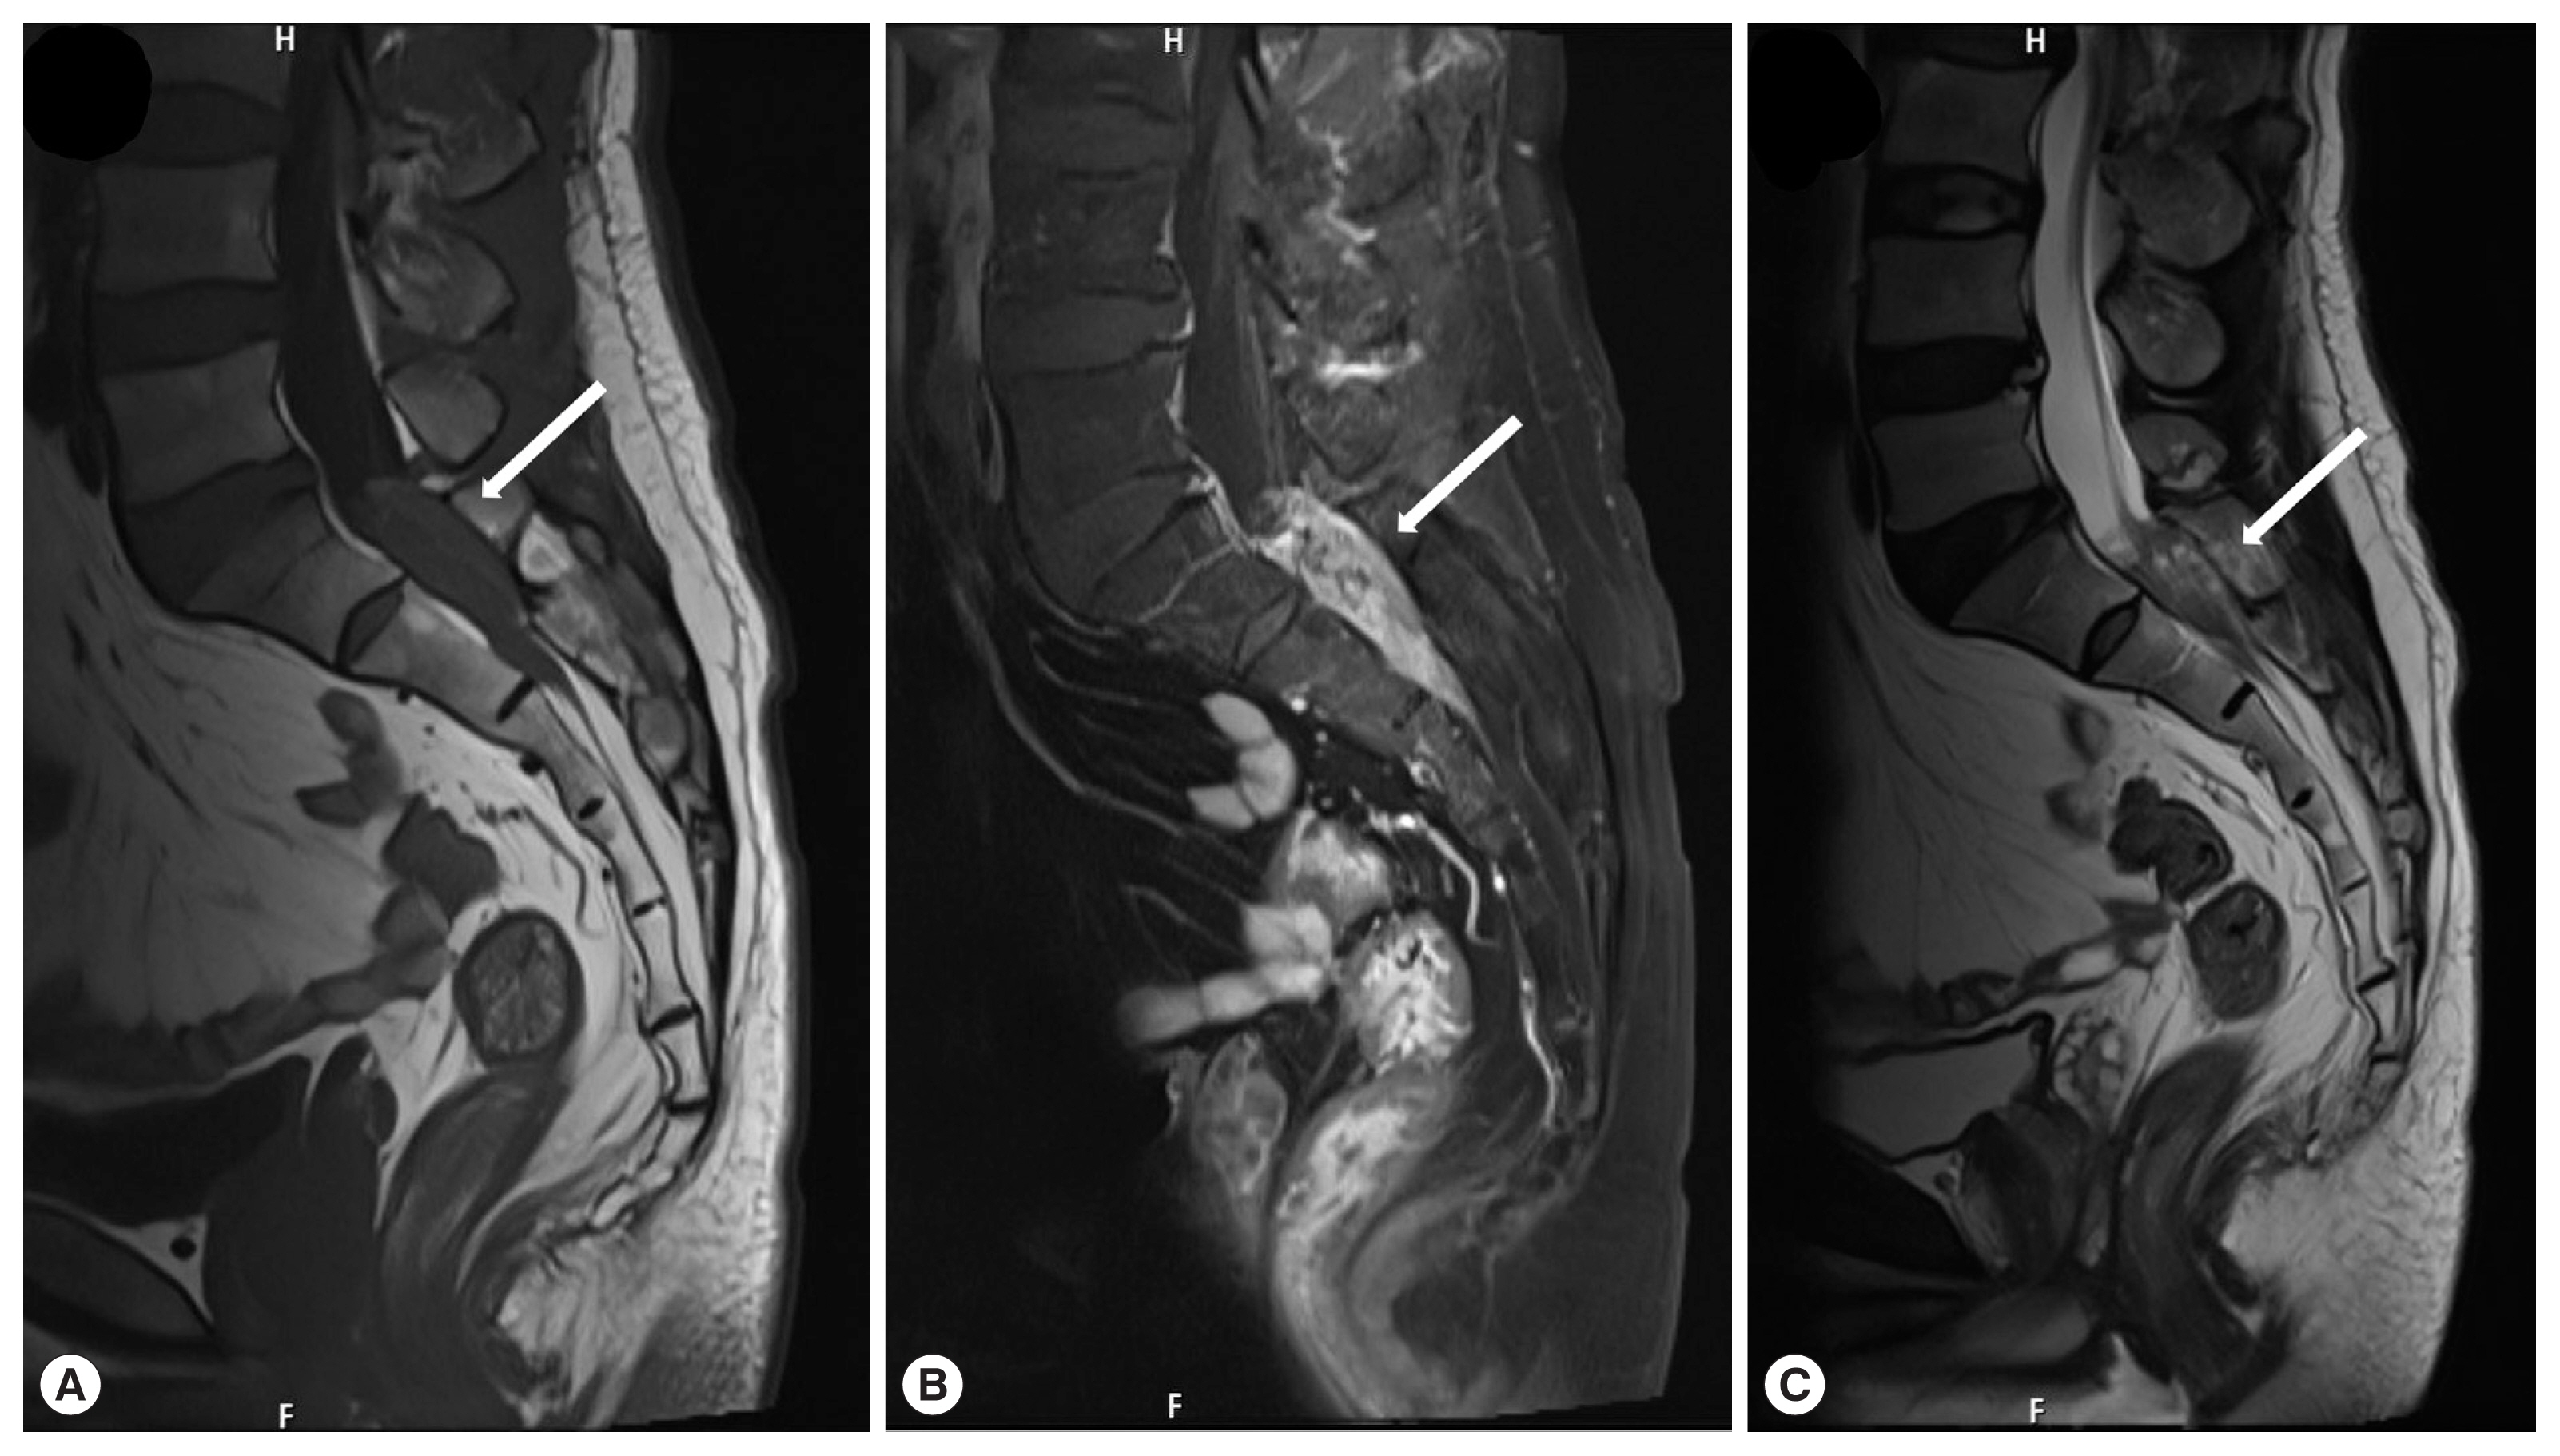

A 56-year-old man presented with a 1-week history of perianal pain. No history of dysuria or difficulties in defecation were reported. And the muscle strength of the bi-upper and bi-lower limbs was grade 5 in the MRC scale. The muscle tonus of the 4 limbs was normal, with normal tendon reflexes in the upper and lower limbs. And laboratory assessment revealed that white blood cell count of 6,200/μl (reference range 4,000–10,000/μl ), with 1.9% eosinophil count (reference range 0.4–8.0%). Further examinations such as blood biochemistry, routine stool examination, and urine analysis were within normal range. MRI of the lumbosacral spine with gadolinium contrast study showed a 1.7×1.5×5.4 cm heterogeneous enhancing mass at the S1–2 level (Fig. 1). We initially considered the possibility of a neoplastic lesion. The patient underwent laminectomy from S1 to S2. On the operative view, we found that the dural tension was very high, the arachnoid membrane was thickened and yellowish-white due to severe inflammation and adhesion. We detected a live worm in inferior margin of L5 (Fig. 2A), proliferative inflammatory granulation tissue (Fig. 2B) surrounding the nerve tissue of cauda equina, which is not easy to remove. We did not remove inflammatory granulation tissue, just only took the worm body out from it.

In the case of cerebral sparganosis, the typical signs on Computed tomography (CT) include hypodensity of the white matter, irregular or nodular-enhancing lesions and small dot-like calcification. MRI findings may include aggregated ring-like enhancement (often 3 to 6 bead-shaped rings), “tunnel sign” with enhancement of lesions, and migration of radiographic lesions as larvae migrate. In our case, the lumbosacral MRI revealed heterogeneous enhancing lesion at the S1–2 level. The gold standard for diagnosis of sparganosis remains histological examination [6]. In addition, IgG antibodies to sparganum from serum or CSF can be detected by ELISA, which has high sensitivity and specificity [7]. However, the diagnosis mainly depends on surgical detection of the worms due to the rare presence of sparganosis. In our case, the ELISA for anti-sparganum antibodies was positive in both plasma and CSF collected on the day after operation.